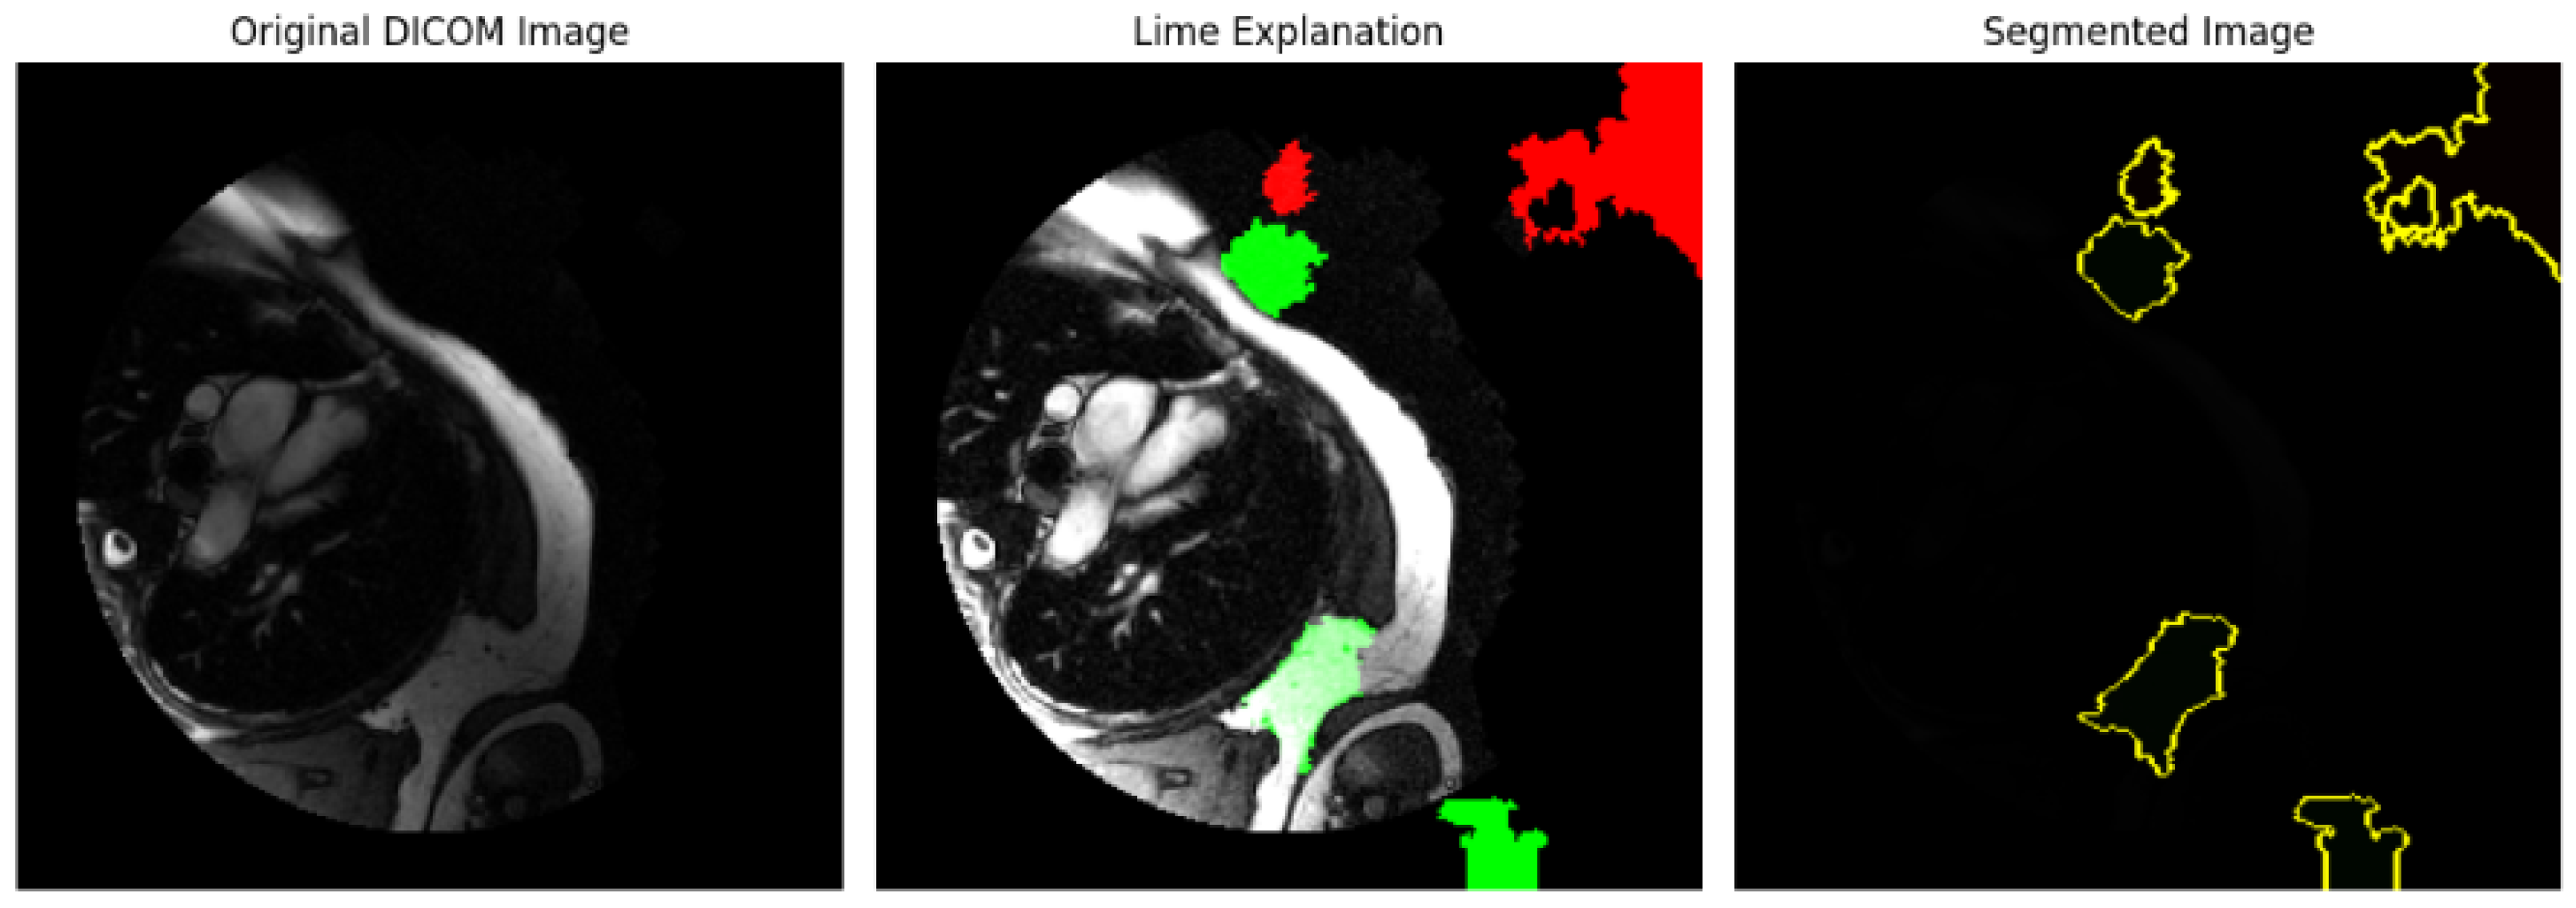

An analysis of the medical images using bounding box, edge detection, and intensity histograms is shown in Figure 5. A rule-based approach was used to generate the masks. However, such an approach would need more learning capacity to adapt to the complex structures seen in cardiovascular heart imaging to maintain bias. Rule-based segmentation (e.g., thresholds or edge detection techniques) limits accuracy and reliability. Such techniques do not learn from data patterns and fail to capture the nuances of complex cardiovascular image structures such as variations across different images, which deep learning models like Mask R-CNN handle effectively.

4.3.2. Mask R-CNN Model

The Mask R-CNN model has been used for object detection and segmentation on DICOM images. Mask R-CNN, a deep learning-based model, can identify objects and produce pixel-wise segmentation masks. The model is used for segmentation and generates masks for the objects detected in each DICOM image. These masks represent areas of interest (potential regions in medical imaging where specific structures or abnormalities are present. Also, the Dice coefficient calculation was used to measure the overlap between the model’s predicted mask and a ground truth mask (which was a placeholder in this code). This evaluation is essential in assessing how accurately the model’s segmentation matches the expected area.

See a segmentation analysis of cardiovascular structures in MRI scans in Figure 6. MRI heart image segmentation masks were overlaid on MRI scans, with each image annotated with a Dice coefficient score. The Dice coefficient, a measure of overlap between the predicted segmentation mask and the ground truth mask was used to evaluate the accuracy of the segmentation models, with values closer to 1 indicating better overlap and thus higher segmentation accuracy.